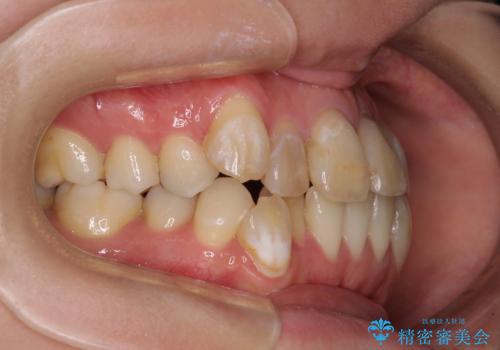

口元の突出感はありませんが、前歯の重なりが著しいため、目立ちにくい表側のワイヤー装置にて、上下左右の第一小臼歯4本を抜歯して矯正治療を行うこととしました。

上顎前歯4本は、以前むし歯により神経をすべて取り除かれており、その影響で既に変色を起こしている状態でした。

4本とも歯根部先端の骨が炎症により吸収していることがレントゲン写真から示唆されたため、矯正治療後に4本を再根管治療し、その後上顎6歯をオールセラミッククラウンにて補綴治療することとしました。